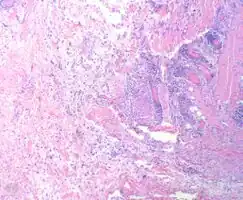

Myxofibrosarcoma-pathology -

Myxofibrosarcoma-pathology